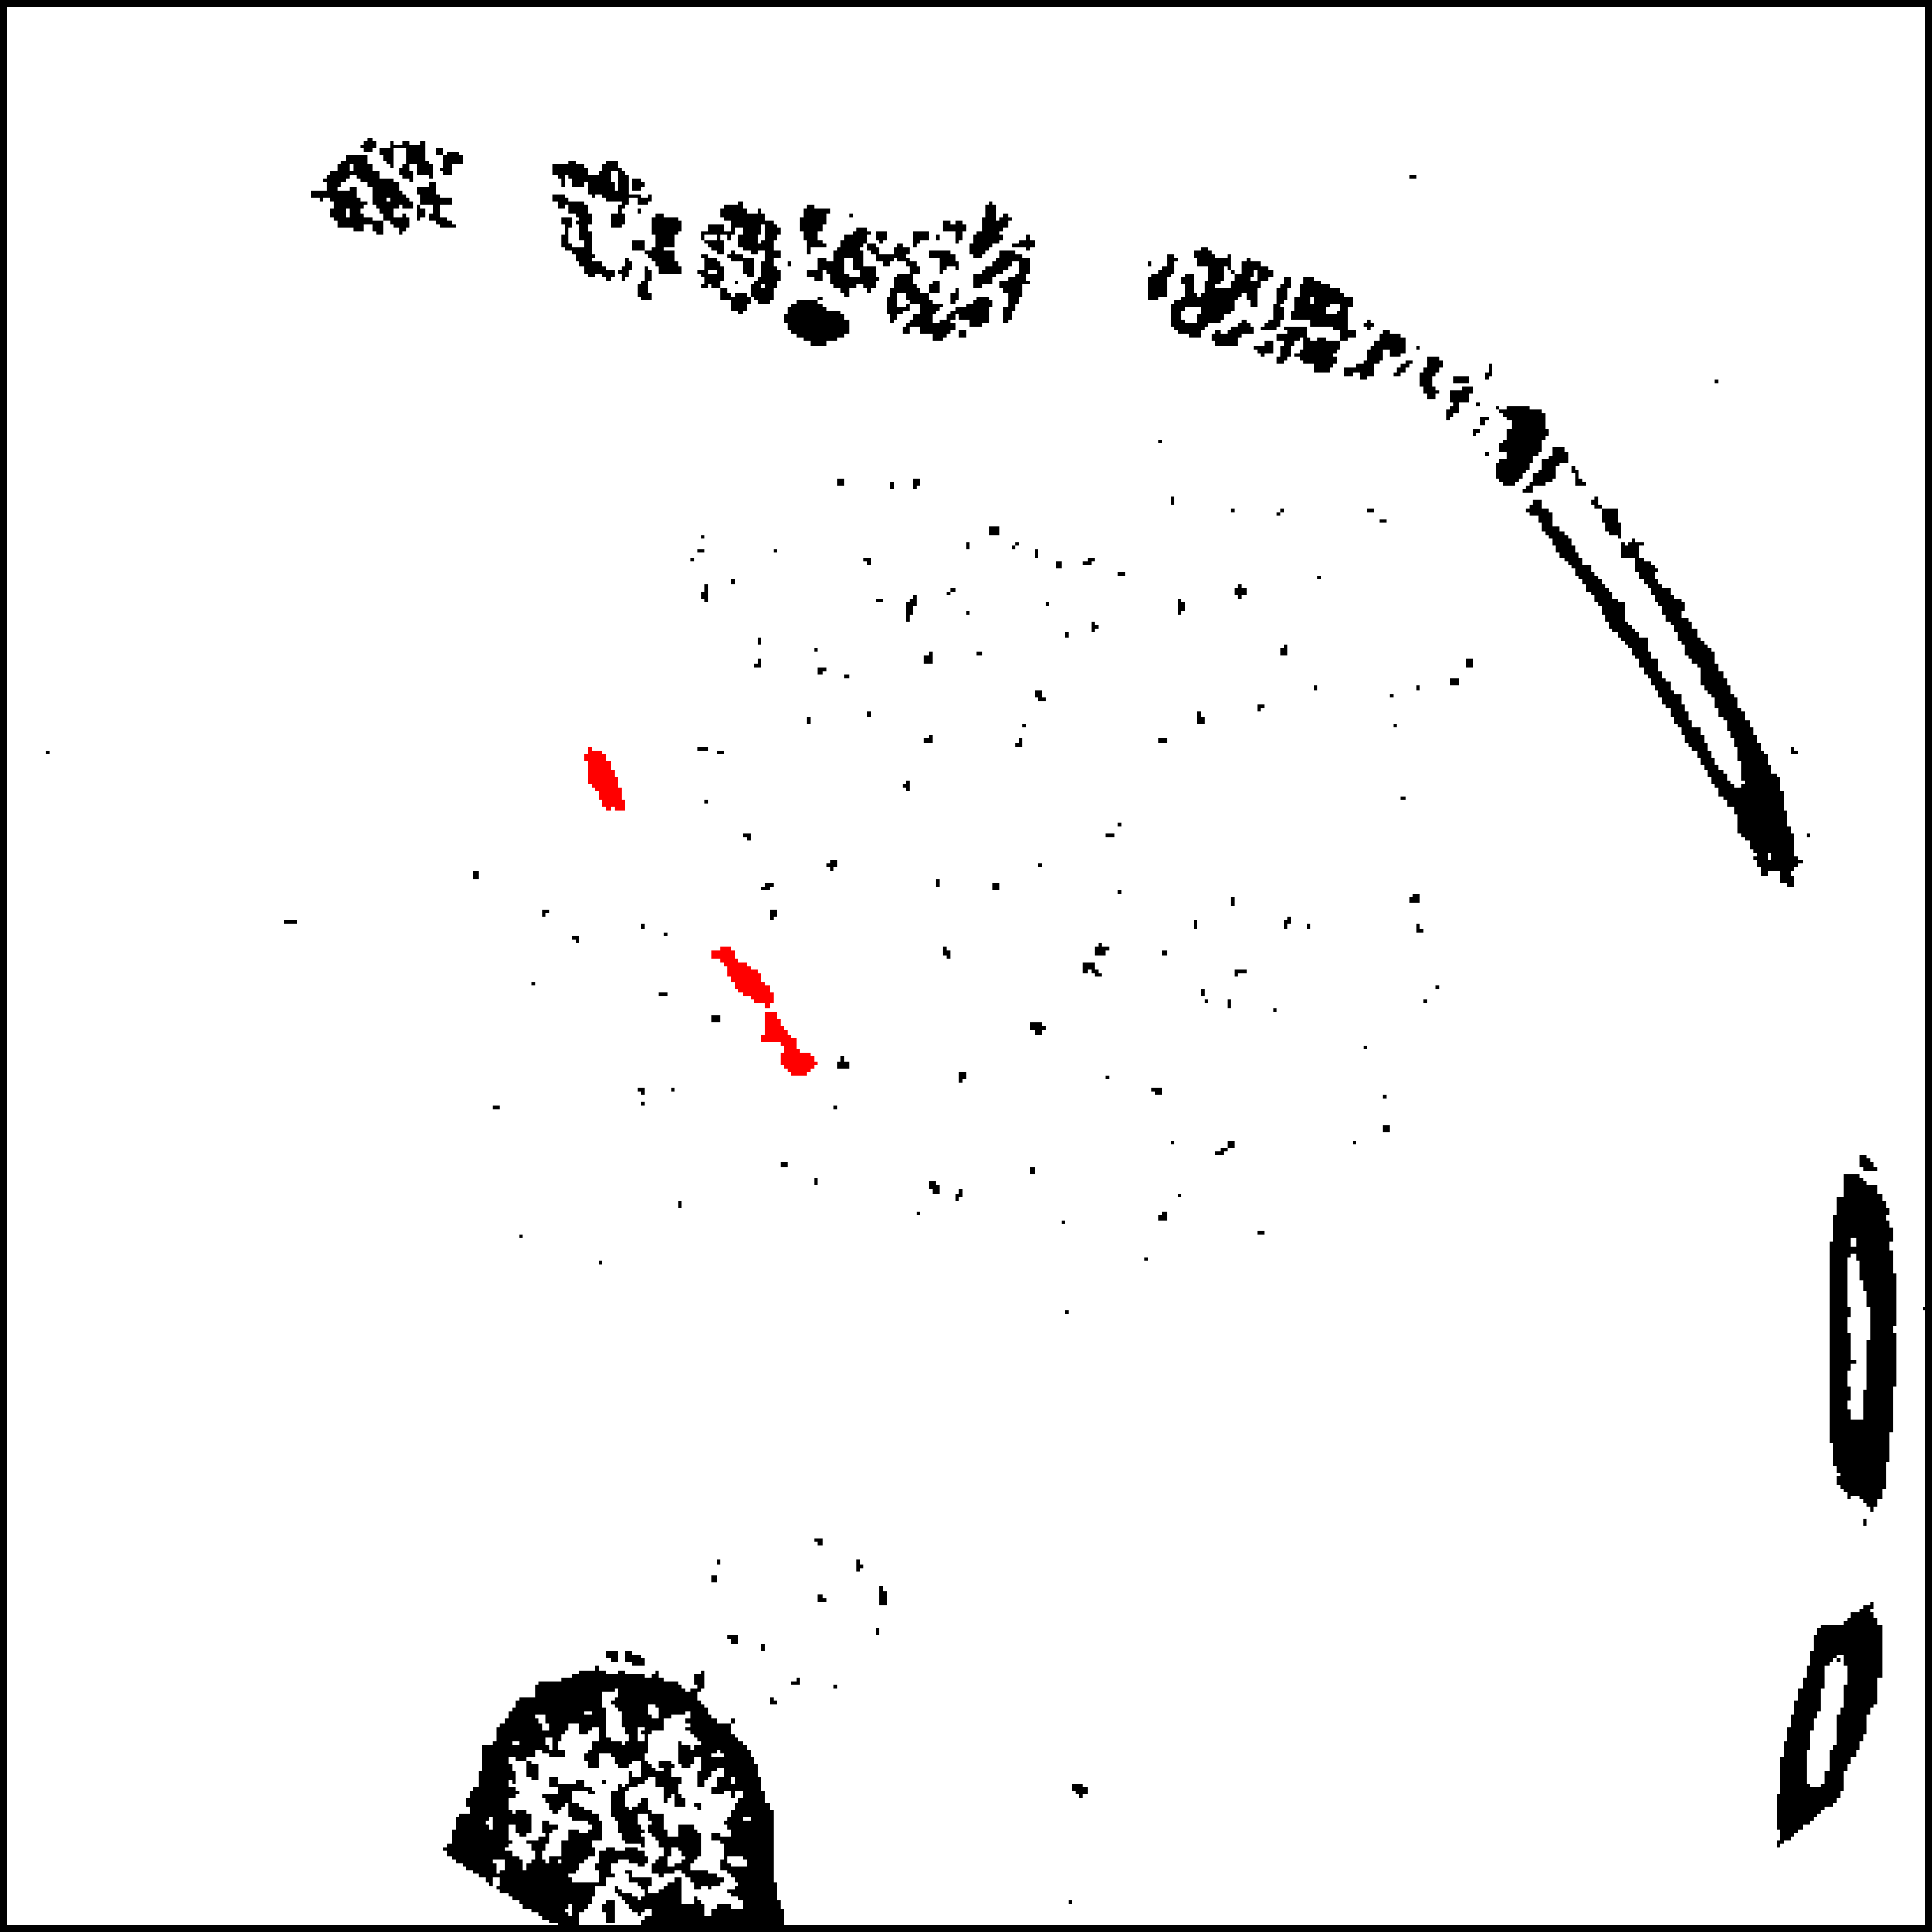

The theory and framework for domain adaptation via adversarial training presented in Sec. 4 has formed the basis for several works in biomedical image analysis. Kamnitsas et al. [52] proposed employing domain adversarial networks for alleviating problematic segmentation due to domain shift between MR acquisition protocols. Extending the basic framework, they proposed multi-connected adversarial nets, which enable the domain discriminator to process information from several layers of the feature extractor (Fig. 10). Empirical analysis showed that this leads to a higher quality domain classifier, hence flow of better gradients to the primary network and improved adaptation. By applying the technique to adapt between two databases of multi-modal MR brain scans with traumatic brain lesions, where one of the modalities differed (Fig. 11), they showed that domain adversarial training is applicable to 3D CNNs for volumetric image processing. This was previously questioned in the literature [53] due to memory constraints.

Refer to caption

Figure 11: Result from Kamnitsas et al [52]. A CNN for segmentation of brain lesions is trained on a database of multi-modal MR scans, which include gradient echo (GE) sequence. The CNN fails when it is applied on another study, where susceptibility weighted imaging was acquired instead of GE. Domain adaptation alleviates the issue.